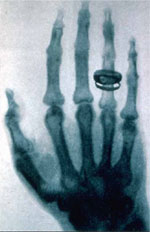

Figura 1. Reproducción de una radiografía de mano tomada en 1896.

Al hacer incidir un haz de rayos X sobre una sustancia, esta se difractará formando un patrón de refracción especial, relacionado con el ordenamiento de sus moléculas. Esta técnica, conocida como difracción de los rayos X, nos permite averiguar la estructura de una sustancia estudiada (por medio de la comparación con patrones de difracción ya conocidos). Uno de las personas que más influyó en el desarrollo de esta técnica fue un inglés, quien al examinar un pedazo de lana, notó que el patrón de los rayos X producido por la lana estirada tenía una estructura diferente al de la lana relajada. Este descubrimiento hizo pensar a muchos en que los rayos X podían ser usados para estudiar la estructura de ciertas moléculas, y en los años 1930, comenzó a usarse esta técnica para analizar la estructura de proteínas. Sin embargo, probablemente el uso más común de los rayos X sea el que todos conocemos: para ver los huesos.